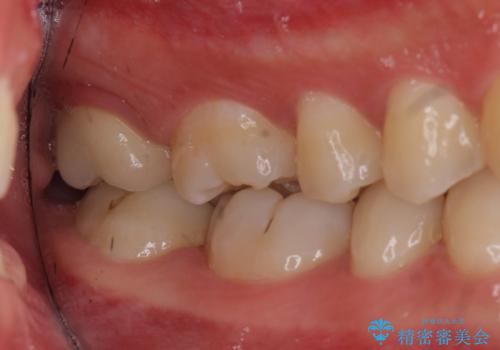

奥歯の虫歯 特殊な形をした歯の治療

- 奥歯が虫歯になり、位置的に詰め物は難しかったため、被せものにする治療を行いました。

頬側に咬頭が一つ多い歯であったのと、歯肉に近い位置が虫歯になっていたため、被せものでしっかり覆う治療を行いました。